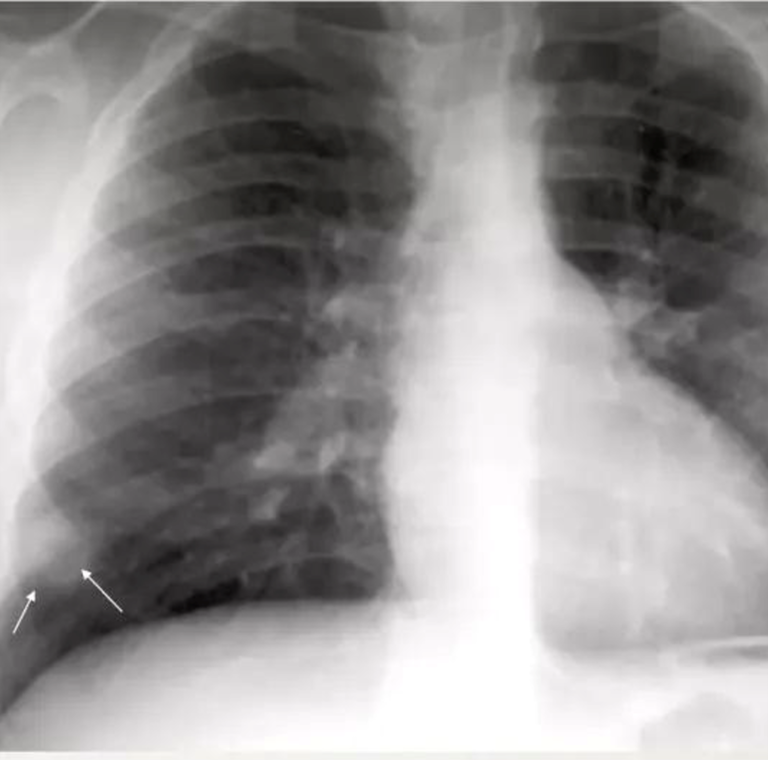

10-year-old child with tuberculosis, shows widening of the right paratracheal stripe

⁠ ⁠Ghon focus may be visualized on the chest radiograph as an airspace opacity

•⁠ ⁠Small tan-yellow subpleural granuloma in the mid-lung field on the right.

•⁠ ⁠Over time, the granulomas decrease in size and can calcify, leaving a focal calcified spot on a chest radiograph that suggests remote granulomatous disease.

• ⁠ ⁠typical of primary tuberculosis in a child

• Airspace consolidation is usually unilateral, is evident radiographically in approximately 70% of children with primary TB.

Pleural effusion is usually unilateral and due to subpleural infection.